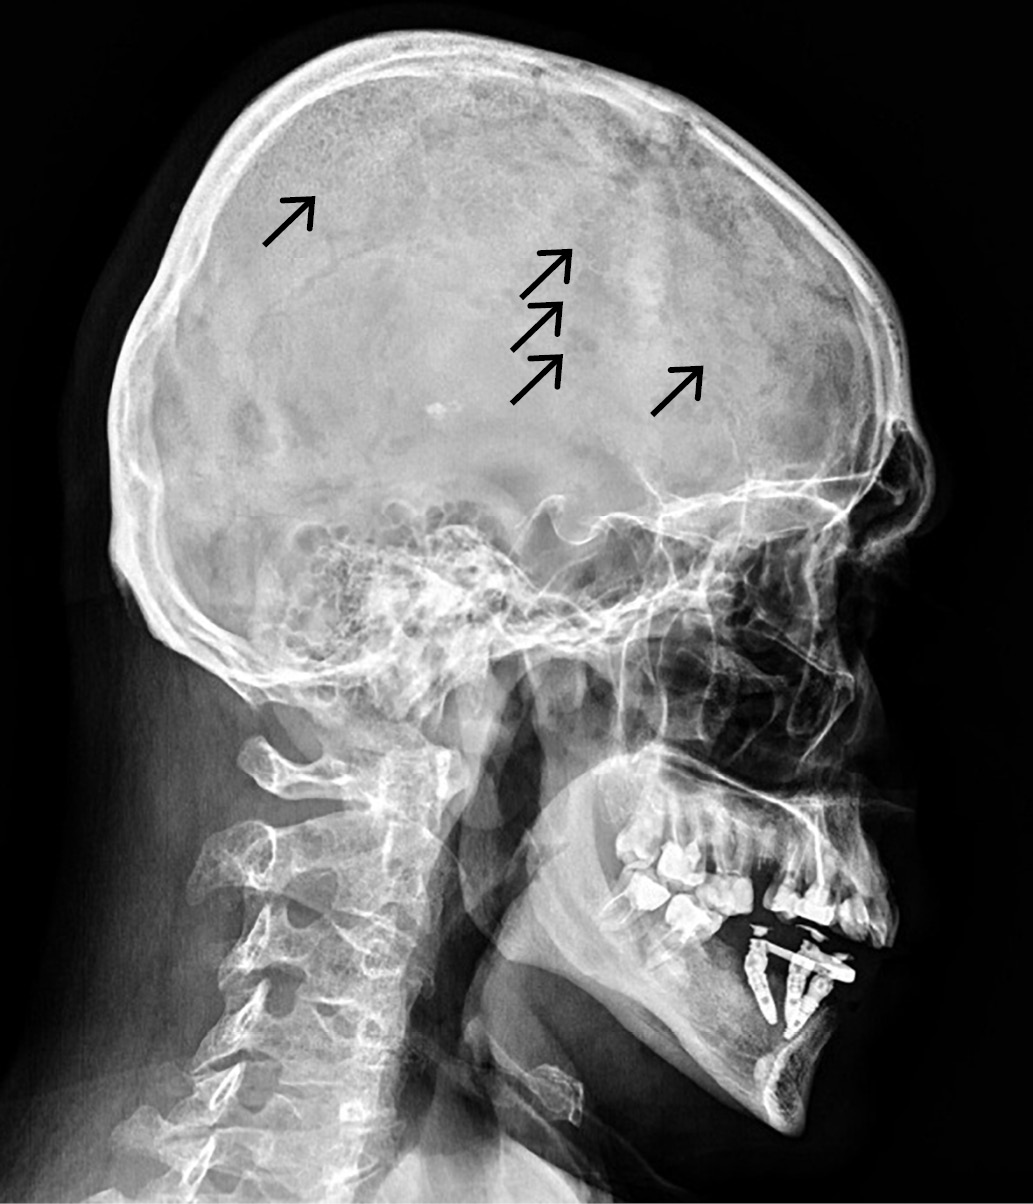

Рисунок 2. Рентгенограмма грудного (А) и поясничного (Б)

отделов позвоночника в боковой проекции пациента Я.

Стрелками указаны очаги литической деструкции в телах позвонков,

в ребрах, особенно в их задних отрезках,

в остистых отростках позвонков по типу «пчелиных сот».

Figure 2. X-ray of the thoracic (A) and lumbar (B) spine

in the lateral projection of the patient I.

Arrows indicate foci of lytic destruction in the vertebral bodies,

in the ribs, especially in their posterior segments, in the spinous processes

of the vertebrae of the type of «honeycomb».

На рентгенограмме боковой проекции грудного отдела позвоночника выявлены компрессия по краниальной и каудальной площадкам с потерей плотной массы Th6 (до 13%), Th7 (до 8%), Th8 (до 4%), выраженный остеопороз и остеохондроз, множественные протрузии межпозвоночных дисков межлопаточной области, на рентгенограмме поясничного отдела позвоночника в боковой проекции выявлены умеренный остеохондроз, ретролистез L3 до 2,2 мм и межпозвоночные протрузии L4–S1. При рентгеноденситометрии получены данные о выраженном снижении минеральной плотности костной ткани с максимальным снижением до -3,8 SD в L1–L4 по Z-критерию.